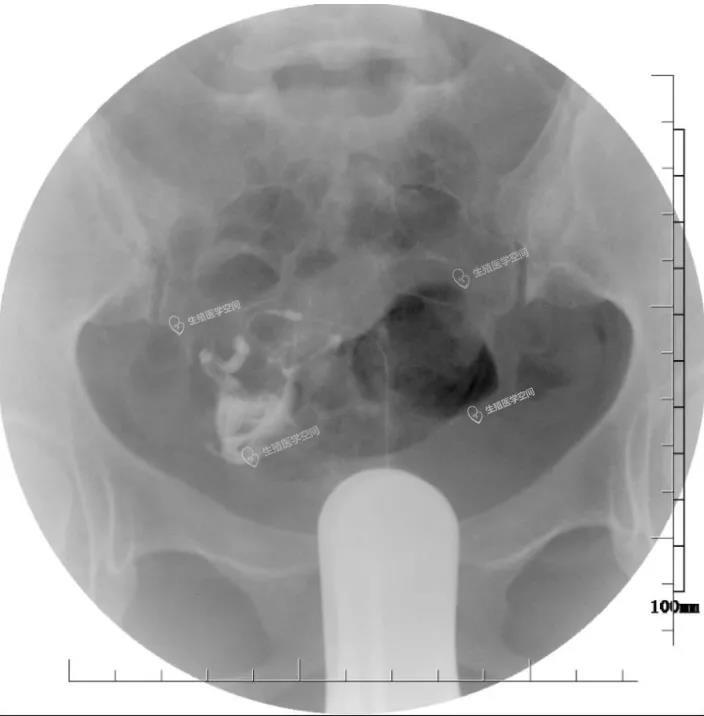

病例5 我记得非常清楚是湖北人,在广东中山市工作。2017年6月29日我做的介入再通术。刘X 37岁 教师,第一胎是个女儿,已经12岁了,为了生儿子做了4次人工流产,还有过一次右侧宫外孕。2016年底在武汉市请北京的专家做宫腹腔镜手术未疏通输卵管。介入疏通。2018年4月3日晚微信同我讲怀孕3个月了。后来心想事成足月生一个健康男婴。